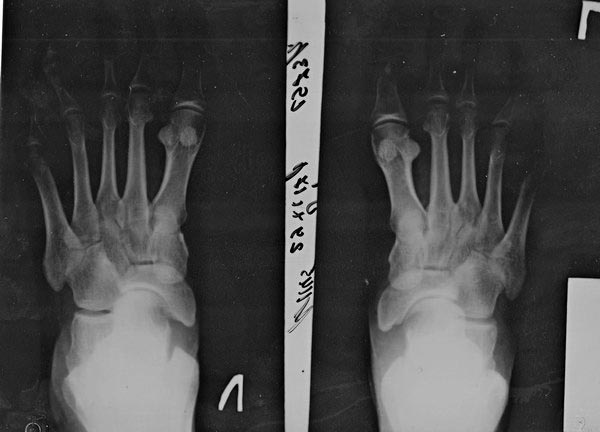

Прошу поделиться опытом в лечении невромы Мортона. Больная - моя

операционная сестра. Болеет около года. Заболевание двустороннее, больше

слева. Сильные боли беспокоят около 4 месяцев. Клинически - типичная

неврома Мортона, но на протяжении последних 4 месяцев, помимо болей,

возникла деформация 4-го луча с обеих сторон,

дугообразное искривление 4 пальца в сторону 5 пальца(видно на

рентгенограмме). По сути сейчас между 3 и 4 пальцами спокойно помещается

карандаш. Типично ли это для невромы? Чем это обусловлено, размером

образования (фиброзирования)?